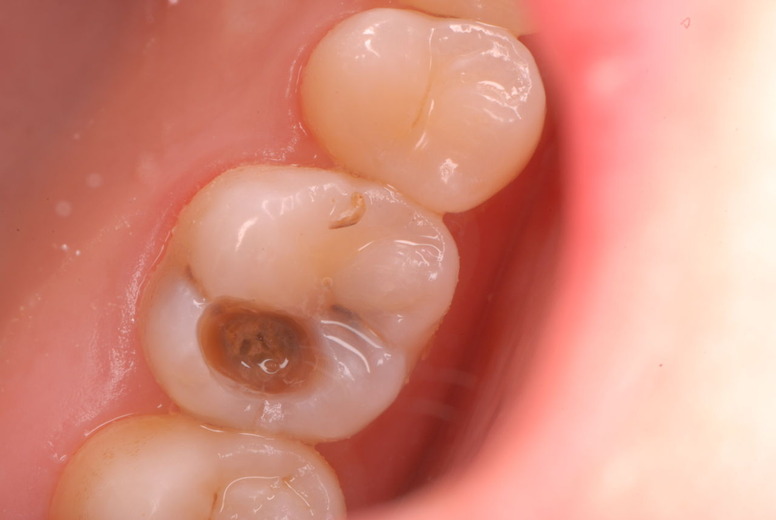

入れ歯の話から入りました。色々不満で注文があるようです。でも話が一段落して口腔内を調べると殆どの歯が重症で抜けそうな歯だらけなのです。

何故歯が悪くなるのか、歯周病で抜けるのか分からなければ何を入れても歯は悪くなり抜けていくのです。

病気を治しましょう。それから差し歯や入れ歯を入れましょう!物を入れれば入れるほど、磨き方や掃除の仕方が上手にならなければ、すぐ抜けてくるのです。